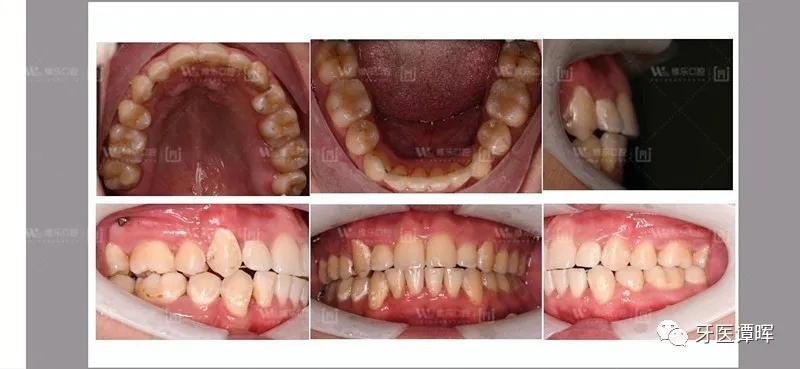

正畸后口内照

正畸治疗结束后通过照片可以看出,上排牙齿及*牙虎**得到了排齐,下牙错位得到了很大的改善排齐后咬合也恢复正常了,最主要的是大大改善了前牙及嘴唇的突度,使脸型更为协调,笑容自信饱满。